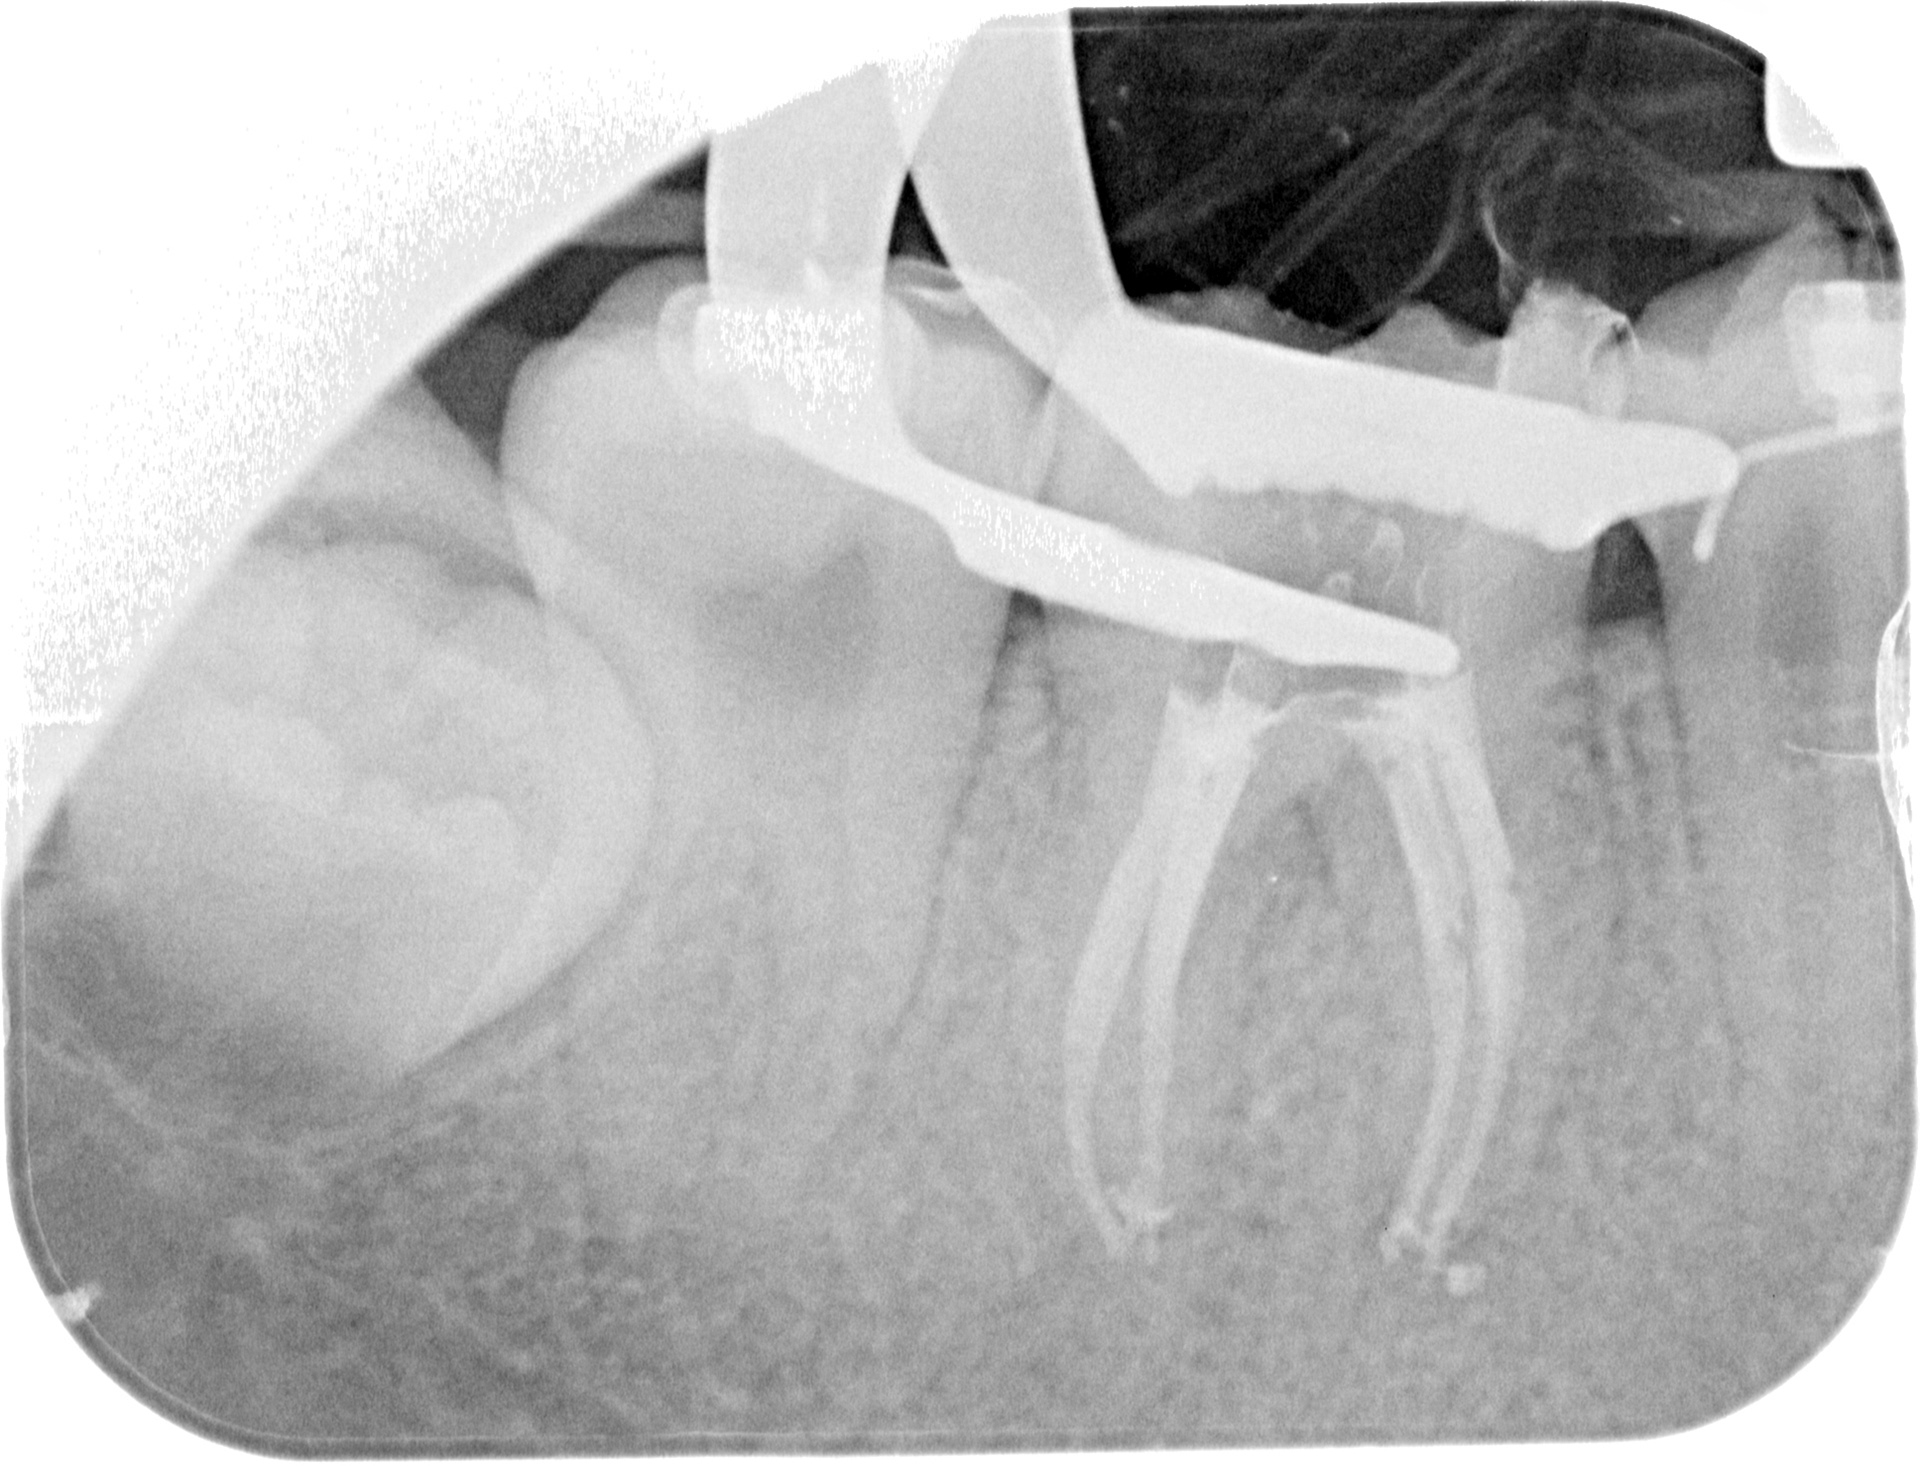

A 46 WITH 4 CANALS

INITIAL

FINAL